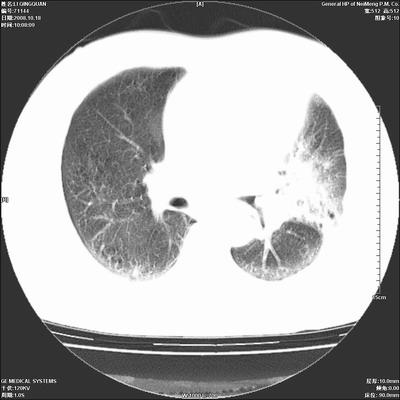

以下是引用duguo在2008-10-19 13:59:00的发言:[br]左肺上叶支气管狭窄,首先考虑中心型肺癌伴阻塞性肺炎\\肺不张.

以下是引用ybing在2008-10-19 12:58:00的发言:[br]左肺上叶阻塞性炎症-建议支气管镜进一步检查除外中央型肺癌

以下是引用随光逐影在2008-10-19 14:31:00的发言:[br]考虑左肺中央型肺癌并左肺上叶阻塞性肺炎,肺不张。